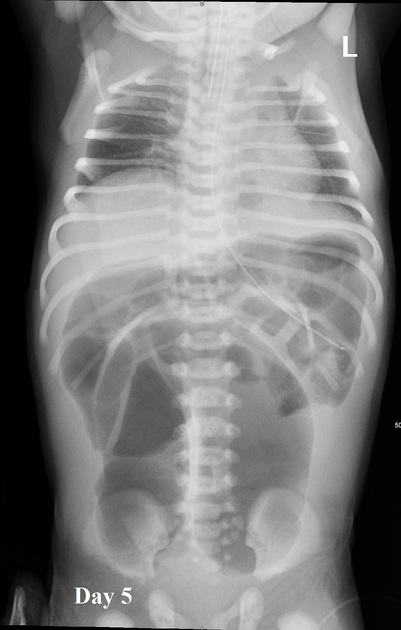

El proceso de neumatización normal del intestino: a los pocos minutos del nacimiento se identifica aire en el estómago, a las 6-12 horas prácticamente todo el intestino delgado contiene aire, y a las 12-24 horas el aire ha llegado al recto.

Los hallazgos ecográficos de íleo paralítico en neonatos pueden incluir varios signos característicos. Según la literatura médica, el íleo paralítico se manifiesta por la dilatación de los intestinos, tanto del intestino delgado como del grueso, sin evidencia de obstrucción mecánica.[1] En el contexto de neonatos, especialmente aquellos con encefalopatía hipóxico-isquémica, se ha observado una disminución o ausencia de peristalsis, lo cual es un indicador clave de íleo paralítico.[2] Además, puede haber un aumento de la ecogenicidad de la pared intestinal y la presencia de líquido libre en la cavidad abdominal.[2] Estos hallazgos son consistentes con la falta de movimiento intestinal y la acumulación de contenido intestinal debido a la parálisis del músculo liso intestinal.

Es importante diferenciar el íleo paralítico de la obstrucción mecánica, ya que los hallazgos ecográficos pueden ser similares, pero la ausencia de peristalsis y la dilatación generalizada sin un punto de obstrucción son más indicativos de íleo paralítico.[1] La ecografía puede ser particularmente útil en la evaluación temprana, ya que permite identificar cambios en la peristalsis y la estructura de la pared intestinal antes de que se desarrollen signos radiográficos más clásicos.[1]